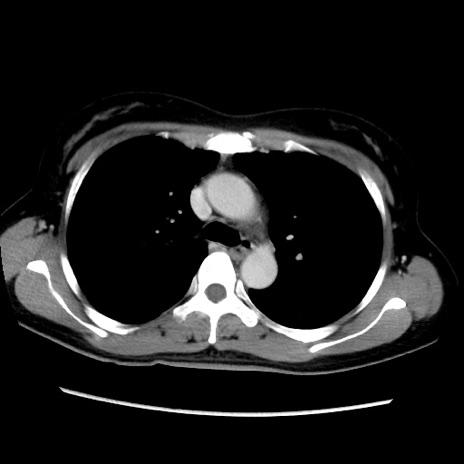

症例39(横断像)

【症例】40歳代女性

【主訴】上下腹部痛

【現病歴】2日目から下腹部痛あり。夜間は痛みで眠れなかった。昨日より上腹部痛と下痢が出現。臥位で痛みは軽快したため、休んでいた。本日になって臥位でも立位でも痛みが強くなってきたため救急要請。

【既往歴】子宮内膜症

【身体所見】部:平坦・軟、左上下腹部に圧痛あり、反跳痛あり。

【データ】WBC 21800、CRP 26.78